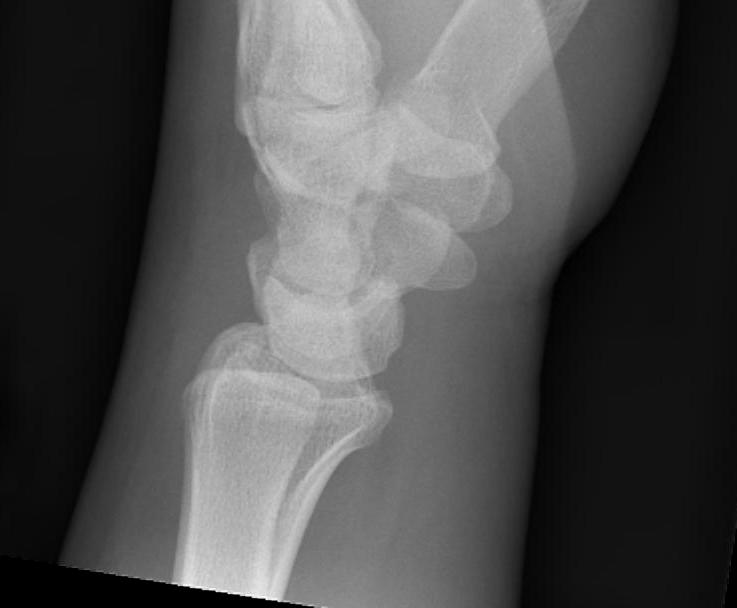

Scaphoid waist fracture 1 mm displaced

Scaphoid fracture with significant displacement

Scaphoid proximal pole fracture